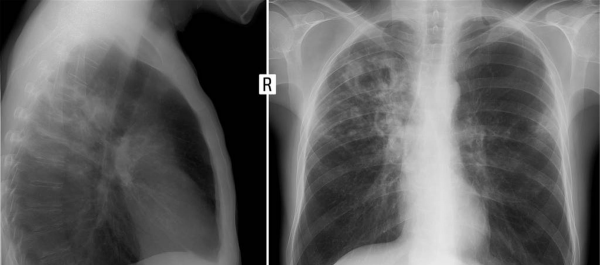

當這些固體顆粒物進入肺部後能完全堵塞肺泡,從而影響肺部的擴張,像上文的王大爺,本來就有肺結節,如果繼續吸茶煙,那麼結節會越來越大,加快肺癌的程序。